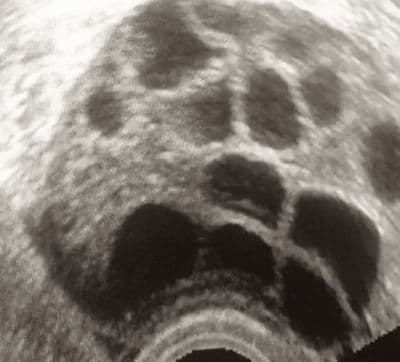

The antral follicle count is a method for ovarian reserve testing using transvaginal ultrasound.

Ovarian follicles are the name given to the small ovarian cysts that contain eggs. At the beginning of a menstrual cycle, using ultrasound you can visualize and even measure these tiny follicles in the ovary. A normal follicle will be less than 9 or 10 mm in diameter.

Studies have demonstrated that as a woman ages, the number of these follicles that are visible at the beginning of the menstrual cycle decreases significantly. It likely represents a decrease in the number of viable eggs that remain in the ovary.

In addition, younger women with a decreased ovarian reserve may also have a smaller number of these follicles. This is demonstrated by the fact that women with a diminished antral follicle count respond poorly to fertility medications, have a greater likelihood of having IVF cycles canceled for poor response, and when they do complete IVF cycles, their pregnancy rates are lower

Studies differ on the exact number of follicles that would be considered decreased but most would be in agreement that a total number of less than four is very low and therefore predictive of decreased ovarian reserve.